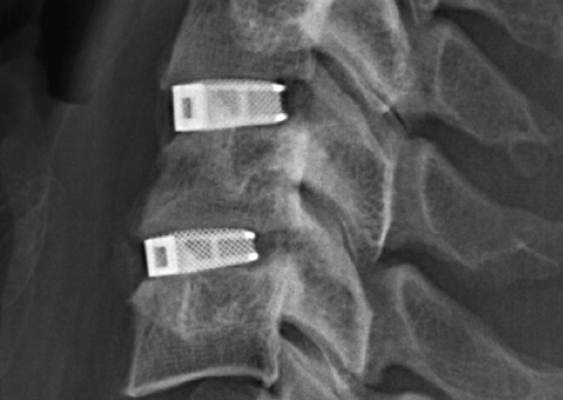

Кейджы межпозвоночных дисков поясничного отдела.

В большинстве случаев проблемный сегмент стабилизируют с помощью металлоконструкций, чаще представленных транспедикулярными системами и пластинами с винтами из высокотехнологичных сплавов металла. В хирургии такая техника называется инструментацией позвоночника. Кроме металлоконструкций, для стабилизации также могут быть применены полимерные устройства, сделанные, например, из углеводородного волокна или резорбирующегося высокомолекулярного биополимера. К отдельной разновидности стабилизирующих вмешательств, которые не причисляют к инструментации, относят установку кейджей имплантатов межпозвоночных дисков.

В преобладающем количестве подобные операции заключаются в достижении полного обездвиживания патологических уровней за счет прочного скрепления двух или более позвонков ригидными конструкциями. Это позволяет позвонкам с течением некоторого времени (от 3 до 6 месяцев) срастись между собой и образовать единый неподвижный костный блок. То есть, на прооперированном поле подвижность между позвонками будет заблокирована, а человек сможет нормально двигаться и ходить, не испытывая при этом боли и прочих неврологических расстройств.